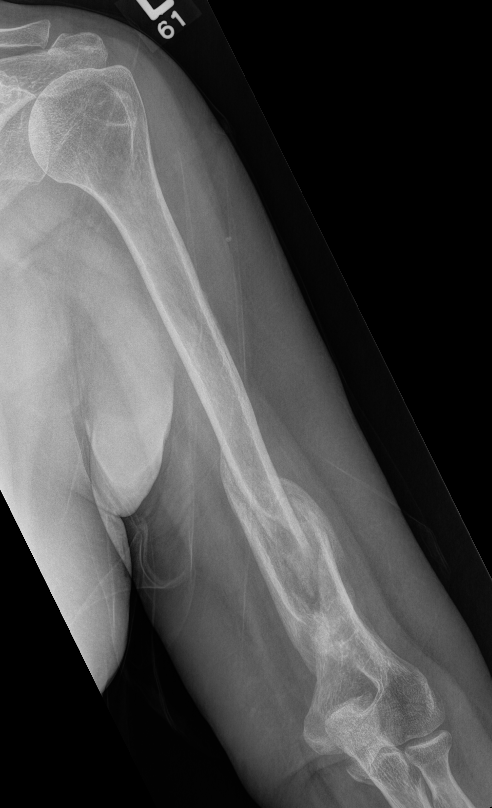

Nonunion in a proximal humerus shaft fracture treated nonoperatively